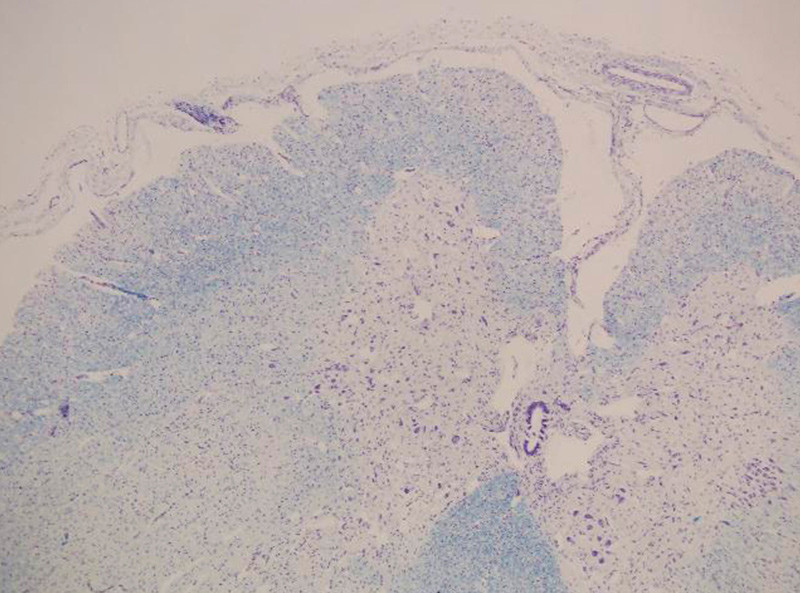

The autopsy revealed a thin diaphragm of only 1 – 2 mm. There was loss of anterior horn cells in the spinal medulla (fig. 1), with very thin anterior roots (fig. 2). There was also a possible loss of fibres in corticospinal pathways throughout the brainstem and in the corticospinal tract laterally in the medulla. Scattered groups of atrophic fibres and scattered hypertrophic fibres were found in the diaphragm (fig. 3). Areas of muscular atrophy were found in the skeletal muscles (fig. 4). The same conclusion was reached that this was a variant of Werdnig-Hoffmann disease.

Figure 1  Anterior horn, possible nerve cell loss (subtle) and slight reactive gliosis. Photo David Schei